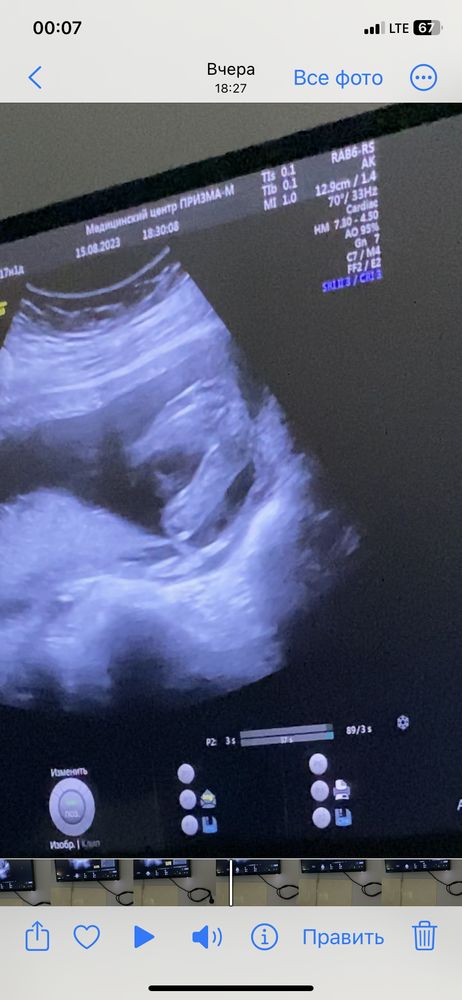

3 скрининг. Есть проблемы😕

Были сегодня на УЗИ. Из хорошего только то, что ставили риск задержки роста плода, но малышка соответствует сроку.

Какие есть проблемы:

1. Увеличение разм